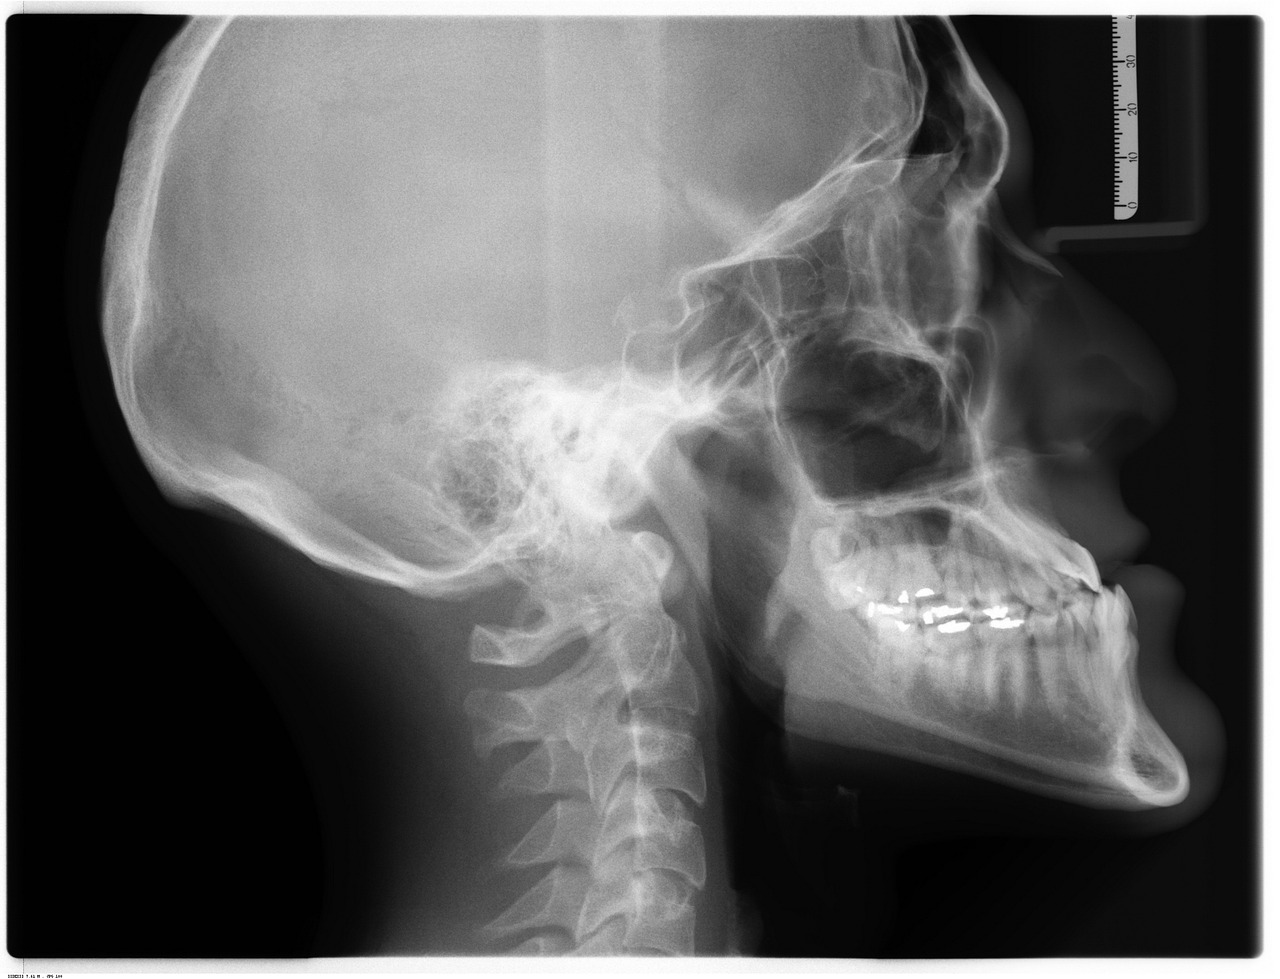

Fractures in bones can lead to severe complications and require urgent medical attention. Accurate diagnosis is crucial for prompt treatment. Common imaging techniques include X-rays, CT scans, and MRIs, which provide essential information regarding the location and severity of fractures. X-rays are often the first-line imaging choice for identifying fractures due to their accessibility and speed. They can quickly show where a break has occurred and how serious it is. In certain cases, conventional X-rays might not provide enough detail, necessitating further imaging. CT scans offer enhanced detail, particularly for complex fractures located in joints. MRI is valuable for soft tissue injuries accompanying bone fractures, providing a clearer picture of the surrounding tissues. Additionally, the use of advanced imaging technologies, like ultrasounds, is gaining popularity due to their non-invasive nature. Correctly interpreting these images demands a skilled radiologist. They collaborate with orthopedic specialists for optimal fracture management. Each imaging type has specific indications, allowing tailored treatment strategies according to fracture characteristics. Thus, timely diagnosis through appropriate imaging is essential for successful fracture management.

Among the various imaging techniques available, each serves a unique role in the diagnosis of bone fractures. X-rays are underlined as the cornerstone imaging tool due to their ability to quickly visualize fractures without the need for extensive preparation. Although they are effective, limitations exist, particularly in complex fractures. Computed tomography (CT) scans bridge this gap, offering three-dimensional images that provide greater clarity for difficult cases and those involving joint spaces. They are particularly beneficial when assessing spinal fractures or complex joints. Magnetic resonance imaging (MRI) is another valuable tool used primarily when soft tissue injuries are suspected alongside fractures. This imaging type does not use ionizing radiation, making it preferable for multiple studies or in scenarios involving children. MRI excels in detailing the surrounding anatomical structures, ensuring comprehensive evaluation. Ultrasound, while less common, is gaining recognition for monitoring and diagnosing fractures, particularly in children due to its safety profile. Each imaging modality has specific advantages and limitations, emphasizing the importance of selecting the right imaging technique based on individual patient circumstances.